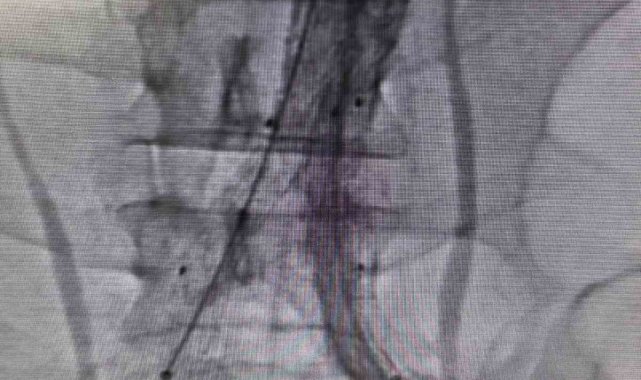

Bilecik Eğitim ve Araştırma Hastanesi'nde daha önce farklı sağlık kuruluşlarına başvuran ancak net bir tanı konulamayan hasta, acil servisinde yapılan detaylı tetkikler sayesinde doğru tanıya ulaştırıldı. Şiddetli sırt ve karın ağrısı şikâyetiyle hastaneye başvuran 39 yaşındaki Mehmet D.'nin acil serviste çekilen ileri görüntüleme tetkiklerinde, kalpten çıkan ana damarın iç duvarında yırtılma olduğu belirlendi. Hayati risk taşıyan bu durum üzerine hasta, kalp ve damar cerrahisi ekibi tarafından acil olarak değerlendirmeye alındı.Hasta, Kalp ve Damar Cerrahisi Uzmanı Op. Dr. Elmas Üreyen tarafından kapalı yöntemle tedavi edildi. Damar içinden girilerek yapılan işlem sırasında, yırtılan ana damarın içine özel bir stent yerleştirildi ve damar içten onarıldı. Açık ameliyata gerek kalmadan gerçekleştirilen bu yöntem sayesinde hasta kısa sürede rahatladı.Tedavi sonrası yakından takip edilen hastanın ağrılarının tamamen geçtiği, genel sağlık durumunun iyi olduğu gözlemlendi. Kontrollerinin sorunsuz seyretmesi üzerine hasta sağlıklı bir şekilde taburcu edildi.

Konuyla ilgili açıklama yapan Op. Dr. Elmas Üreyen, "Bu tür damar yırtılmaları ani gelişebilen ve zamanında müdahale edilmezse hayati risk taşıyan durumlardır. Hastamızda erken tanı koyarak kapalı yöntemle müdahale ettik. Açık ameliyata gerek kalmadan yapılan bu işlem, hastanın hem daha hızlı iyileşmesini hem de günlük yaşamına kısa sürede dönmesini sağladı. Hastanemizde, ileri teknoloji tıbbi cihazlar ve deneyimli hekim kadrosu ile bu tür yüksek riskli damar hastalıklarının tanı ve tedavisi başarıyla gerçekleştirilmektedir. Kapalı yöntemlerle uygulanan bu tedaviler, hastalara daha konforlu bir süreç sunarken, iyileşme süresini de önemli ölçüde kısaltmaktadır" dedi.